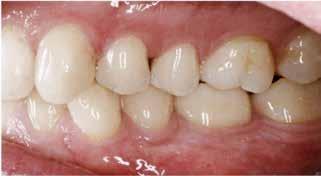

Klinisk undersøgelse viste et tandsæt med enkelte restaureringer, men med slitagedefekter okklusalt/incisalt på samtlige tænder fra 6’er til 6’er i over- og underkæbe (Fig. 2). Defekterne strakte sig tydeligt ind i dentinen. Baseret på anamnesen og de kliniske fund blev erosion set som hovedårsagen til tandsliddet, mens attrition formodedes at være en medvirkende faktor.

Grundet betydeligt tab af emalje, blotlagt dentin, hypersensitivitet samt nedsat funktion og æstetik blev der planlagt en restaurativ behandling med komposit uden ændring af den